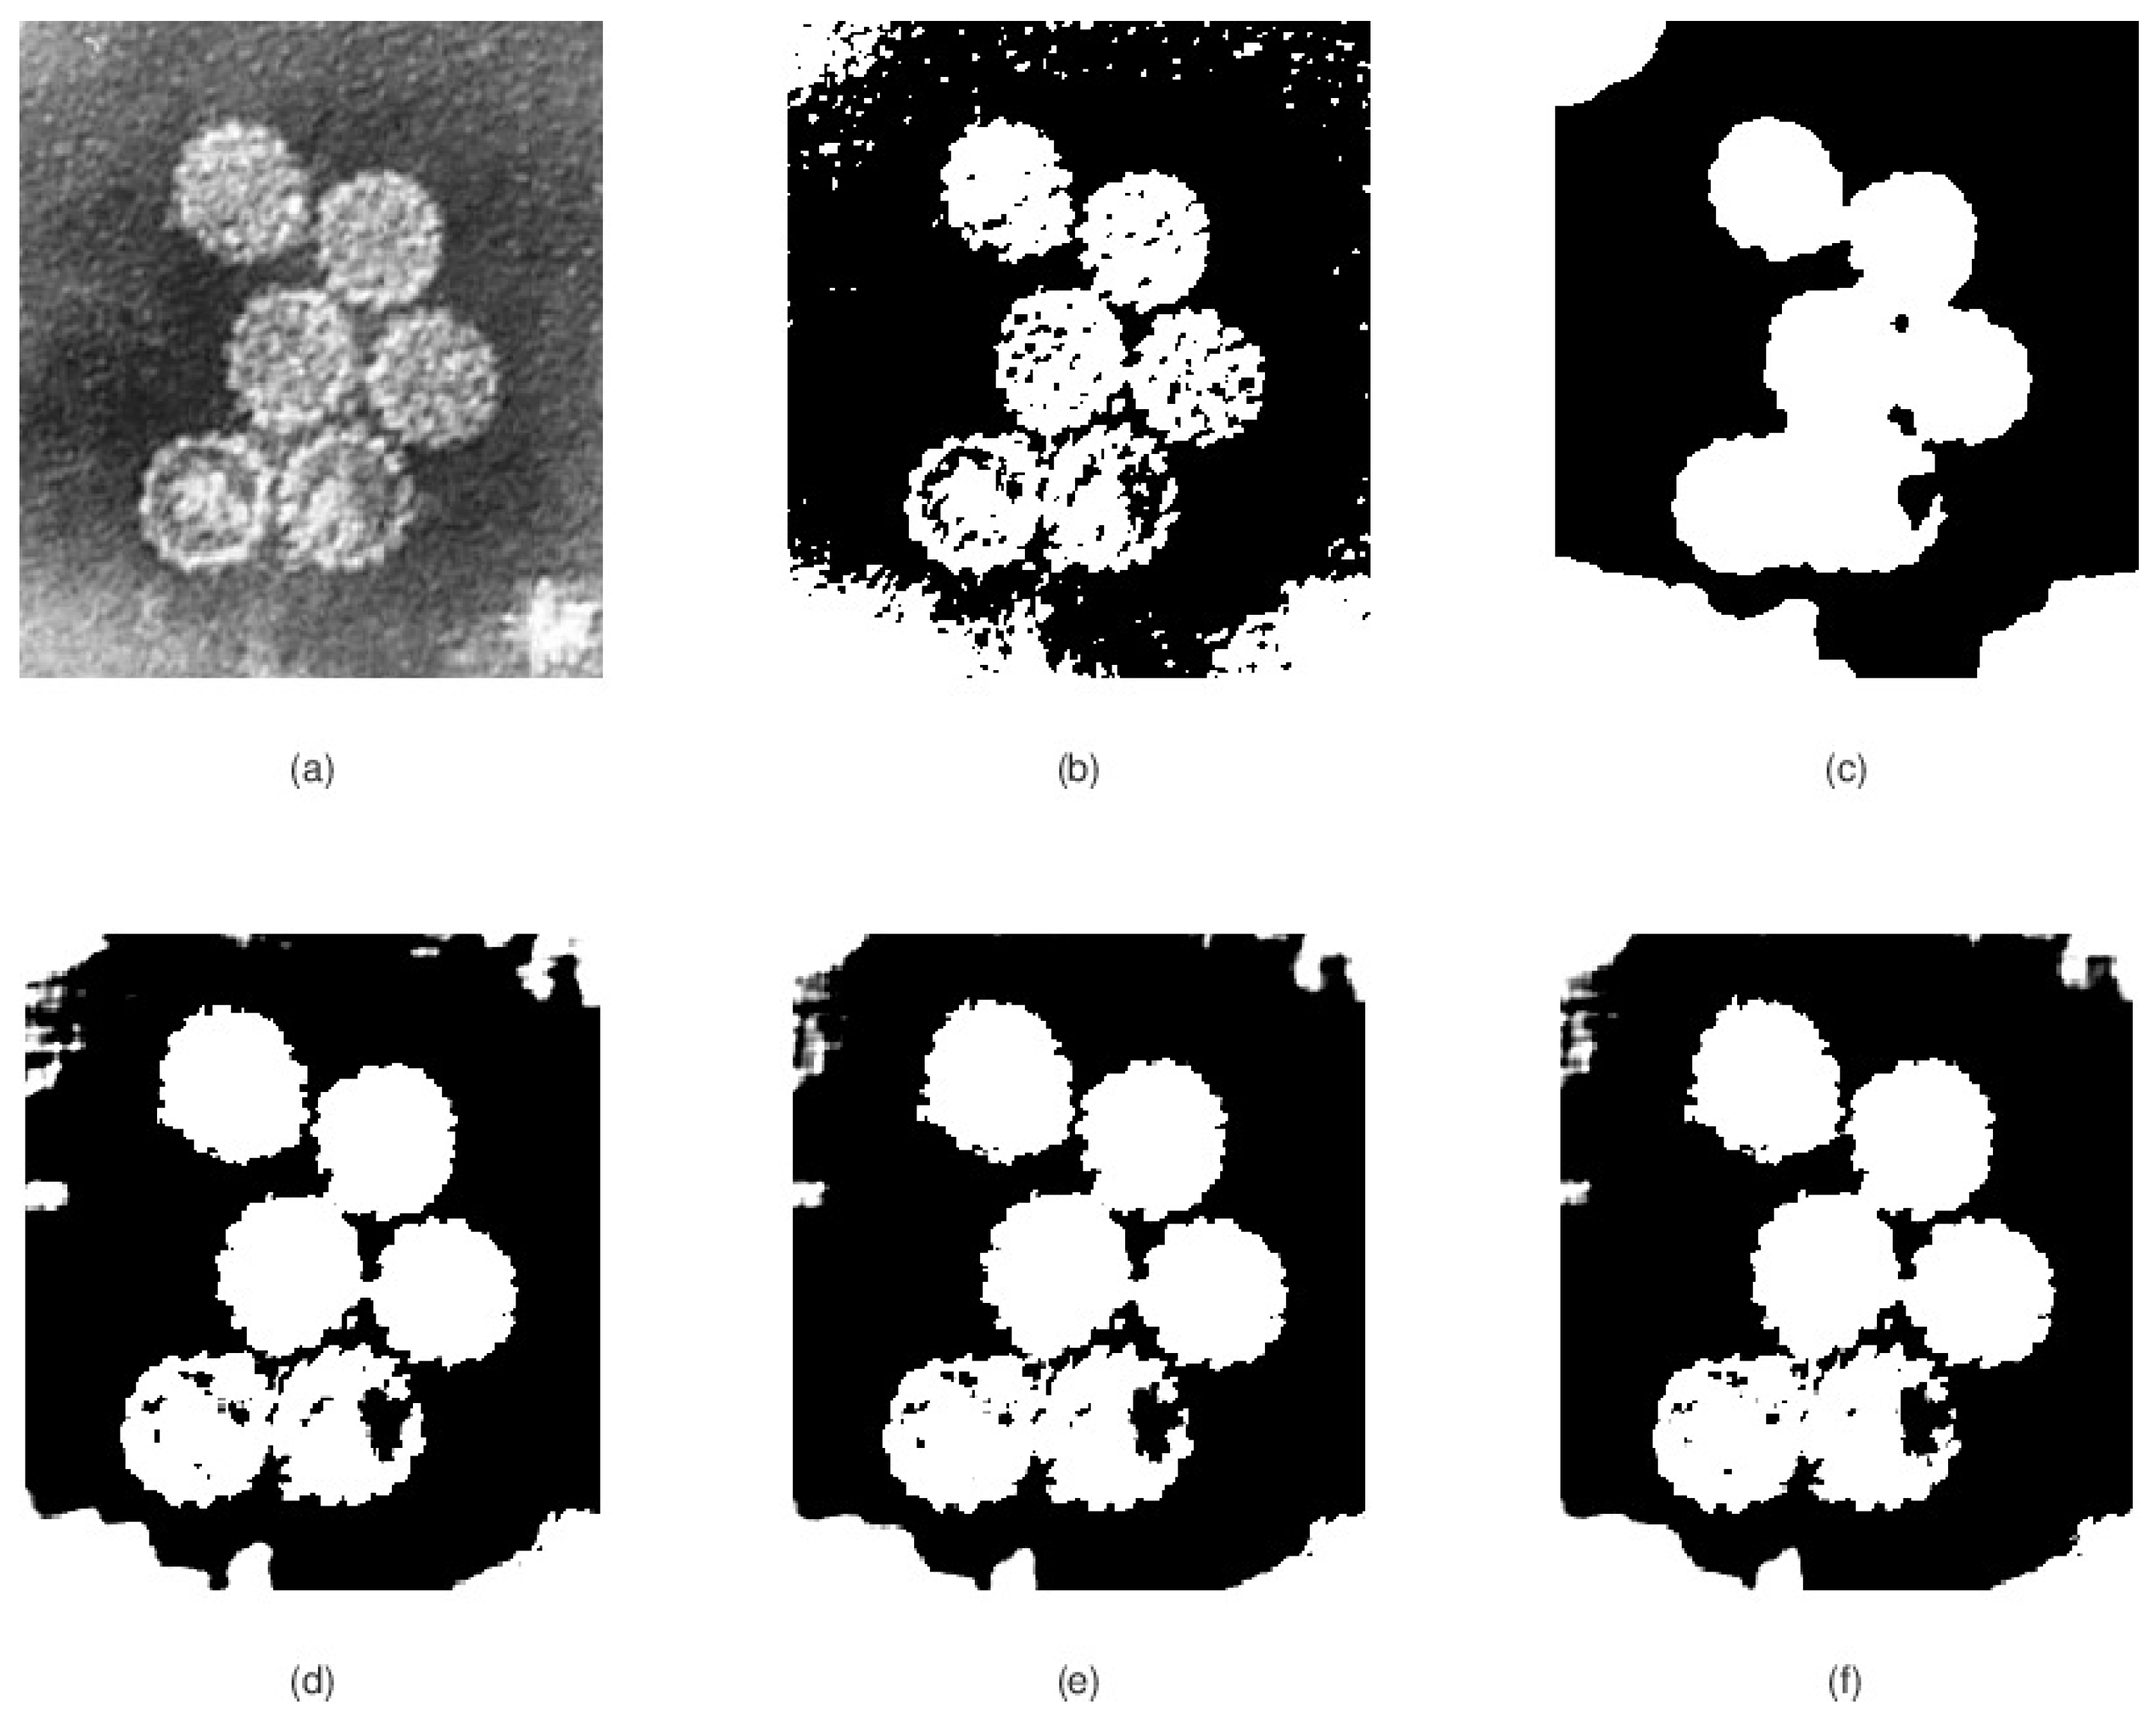

3.2. Experimental Results

- Two two numerical schemes (47) and (48) are constructed to approximate the solution of the mathematical models (31) and (32) (local and nonlocal case).